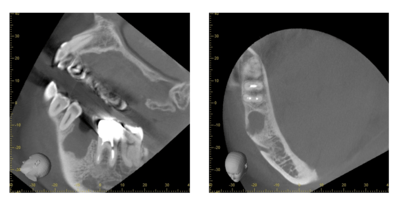

CT像①

CT像②

説明:

CT像です。根の中央を超えて虫歯が広がっているのがわかります。そこに上の親知らずを移植することに

しました。